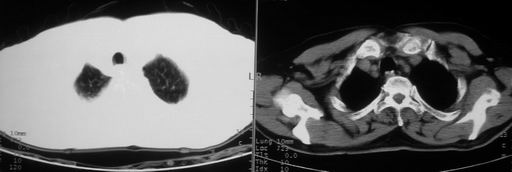

男,78岁,咳嗽、咳痰、发热入院,抗炎治疗一周后已退热,咳血似痰。

10月9日片:

ct左肺下叶大片状高密度影,病变密度不均,界限不清,左侧胸腔积液,治疗后复查临床症状好转而影像学表现病变有发展,还是首先考虑感染性病变,复查时间短附合感染性病变的病理改变。

两肺炎症感染(以左肺下叶为著),双侧少量胸腔积液;建议继续抗炎治疗。